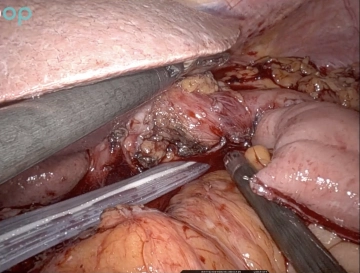

10. Skelettierung und Absetzen des oralen Restmagens

514_10.jpg

Nun wird beginnend am Hiatus oesophageus die kleine Kurvatur des Magens über etwa 4 cm von den Gefäßen und Lymphknoten befreit. Anschließend wird das Omentum nach kaudal weggehalten und es wird unter Schonung der linksseitigen gastroomentalen Gefäße auf die große Kurvatur zuskelettiert. Oral davon wird ein sehr kleiner Anteil des Omentums, in dem die oralen Vasae gastricae breves zum oberen Milzpol ziehen, belassen.  Anschließend wird über den 12mm Robotik Trokar ganz links mit meistens zwei grünen 60er Robotik Magazinen der Magen abgestapelt. Die Länge des Restmagens beträgt etwa 8 cm an der großen und 4 cm an der kleinen Kurvatur.